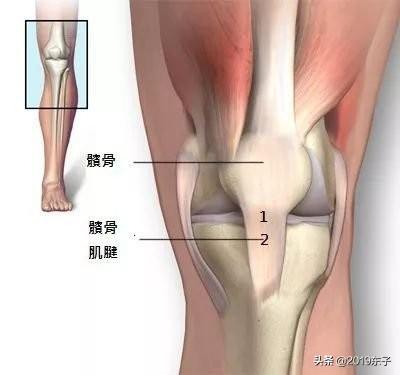

Les femmes jouent le rôle de reproductrices, le bassin des femmes est donc relativement plus large que celui des hommes, ce qui entraîne également certaines anomalies dans la ligne de force de l'articulation du genou, que nous mettons généralement sur le compte de la ligne de force de l'articulation du genou.L'angle où la ligne entre le point médian de la rotule et la tubérosité tibiale croise la ligne d'appui de la traction du quadriceps s'appelle l'angle q.L'angle q normal est de 10 à 15° chez l'homme et de 12 à 18° chez la femme. Plus l'angle q est grand, plus la rotule a tendance à se déplacer latéralement. Plus l'angle q est grand, plus la rotule a tendance à se déplacer latéralement. Plus l'angle de flambage est grand chez les femmes, plus le frottement entre la rotule et son fémur postérieur est important pendant l'accroupissement, ce qui explique pourquoi de nombreuses femmes sont très sujettes aux douleurs fémoro-patellaires latérales.

Bien qu'il puisse sembler à tout le monde que l'angle q chez les femmes n'est que de 3° supérieur à celui des hommes, ces 3° d'anomalie pour la délicate articulation du genou suffisent à rendre les femmes sujettes à des douleurs au genou, sachant que dans laUne déviation de 1° lors d'une chirurgie de remplacement du genou peut avoir des conséquences irréversibles。

Les muscles, les "câbles d'acier" qui protègent les os.Les muscles perdent de leur force et les os sont surchargés. Lorsque les muscles perdent leur force, les os sont surchargés de poids, ce qui entraîne toute une série de problèmes, notammentLa force des muscles de la jambe est très importante pour un os aussi lourd que l'articulation du genou.。

Ci-dessus, nous voyons que les muscles et les tendons travaillent ensemble pour protéger l'articulation du genou. D'une manière générale, siUn rétrécissement important de ces deux muscles au-dessus du genou n'est pas loin d'un problème de genou.